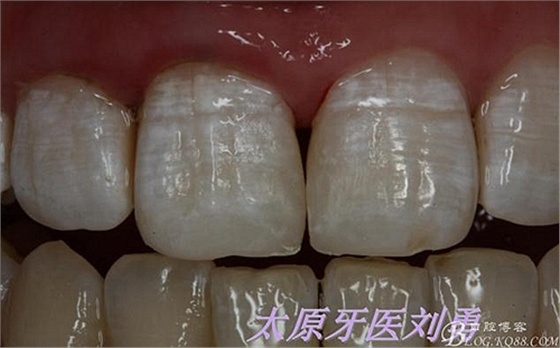

最后附一例樹(shù)脂關(guān)閉牙間隙的病例。具體操作不做詳細(xì)描述。

術(shù)前如下:

術(shù)后即刻如下圖:

術(shù)后5小時(shí)復(fù)查如下圖: